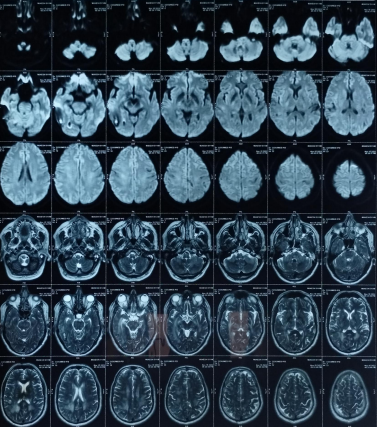

Early-onset dementia (onset before age 65) is a thought-provoking ailment with many possible causes, including early-onset familial Alzheimer’s disease, frontotemporal lobar degeneration, Parkinson’s dementia, Lewy body dementia, disorders of amino acid and organic acid metabolism, leukodystrophies, lysosomal storage diseases, disorders of metal metabolism, and mitochondrial diseases [6]. In our patient, the history, physical examination, laboratory investigations, and neuroimaging were not suggestive of these causes and prompted the search for a rare etiology. The most common MRI finding associated with CADASIL is basal ganglia and white matter hyperintensities in T2-weighted sequences that start as punctate or nodular foci and then often become confluent, extensive, and usually symmetrical, mainly in the periventricular region, anterior temporal pole, external capsule, the centrum semiovale, and frontal and parietal areas. In our patient, diagnosis was made mainly from MRI findings as seen in fig. 1, 2.

Fig. 2: Extensive hyperintensity on T2W/FLAIR sequence is seen in bilateral thalamus and basal ganglia, both cerebellar hemisphere, mid brain, pons and in deep white matter of both cerebral hemispheres